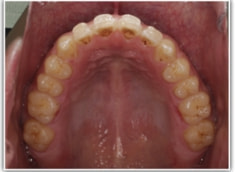

開咬(かいこう:オープンバイト)ケース

治療法:表の矯正(T21ブラケット)

(インプラントアンカーや外科矯正は行わず、エラスティックと機能訓練のみ)

治療前

治療後(2年2ヶ月後)